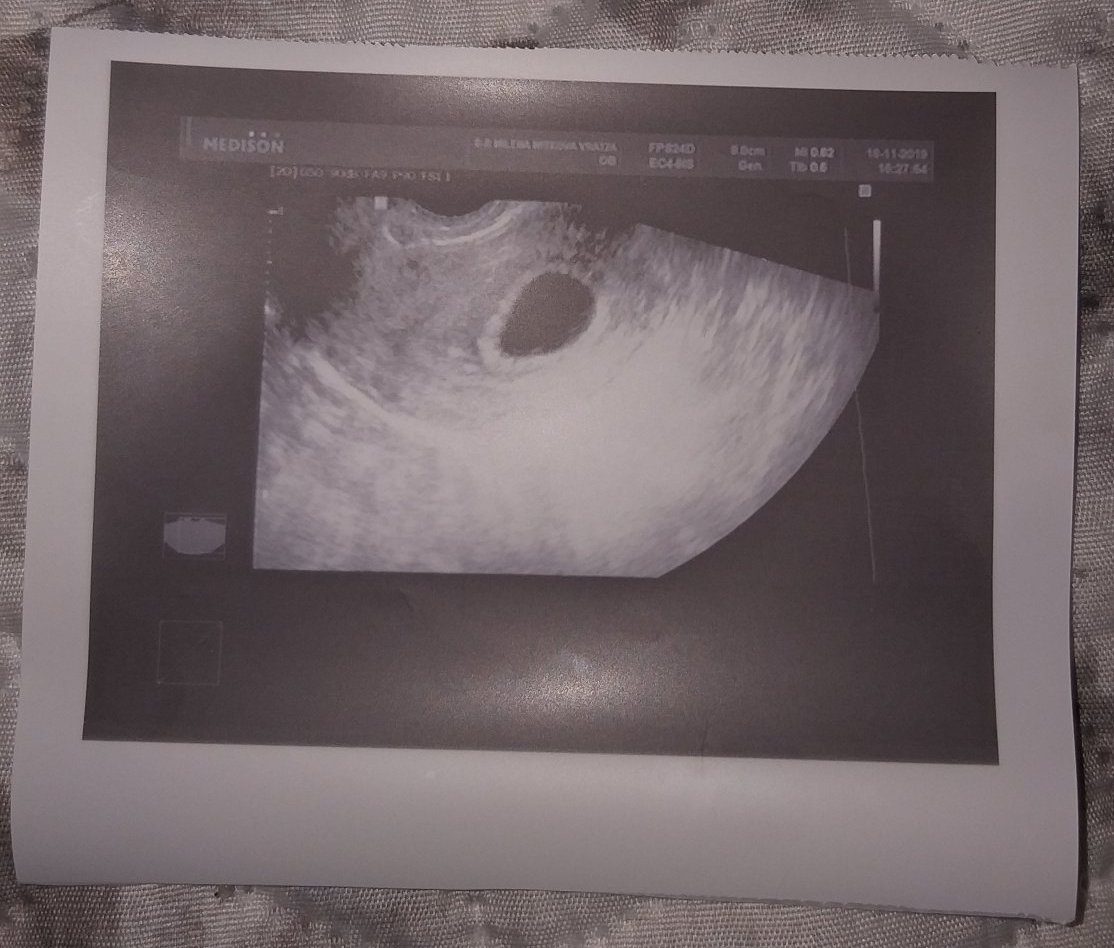

ето и снимка от ехографа ,плодния сак е добре оформен иначе .. не се стърпях и записах час при друг АГ за утре ,дано там да се види нещо по обнадеждаващо